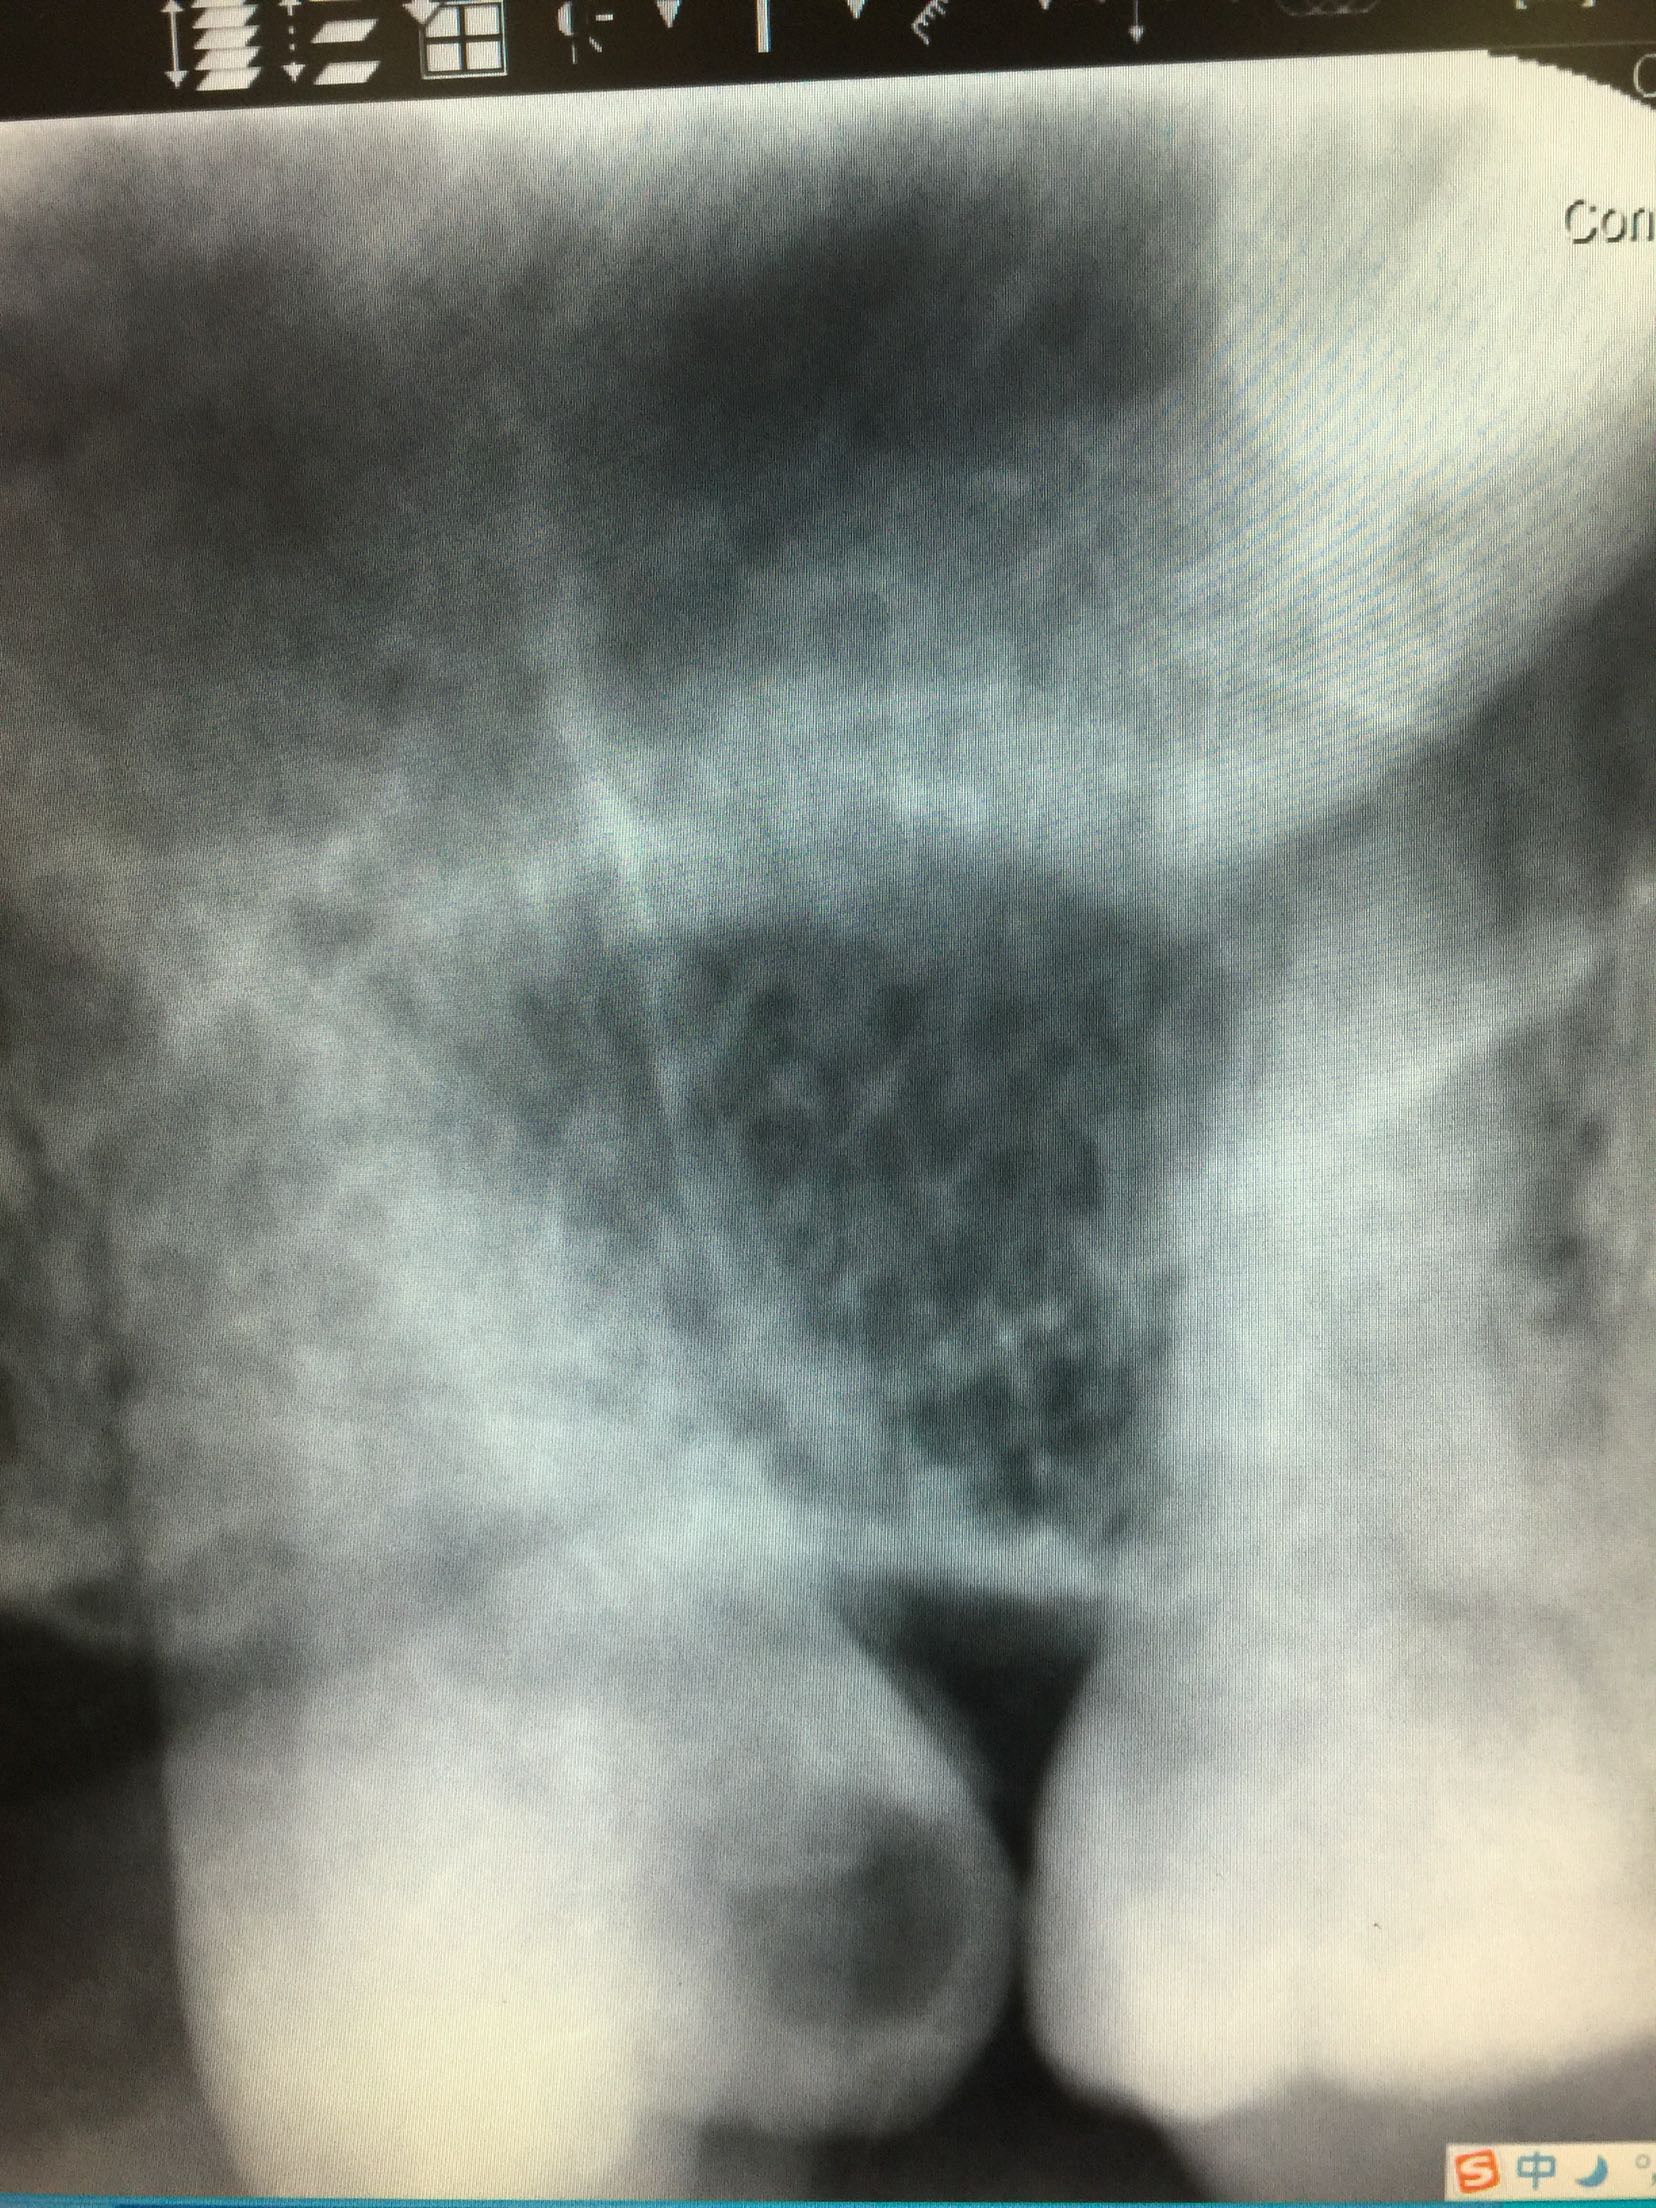

检查:全口卫生尚可,牙石+,软垢+,牙龈正常。18牙近中倾斜,近中邻合面龋,内有大量软龋,深达牙本质深层,已累及髓腔,冷+,探-,叩-,松-。颊侧牙龈未见异常。 17牙缺失,缺牙间隙小,无明显骨尖,对合牙无伸长。 X线:18牙近中邻合面可见龋坏,累及髓腔,未行根管治疗,根尖区未见暗影,牙槽骨吸收至颈部1/3。

诊断:18牙牙髓炎 17牙牙列缺损 治疗计划:因17牙缺牙间隙小,暂不行修复 18牙行去髓术 治疗:碧蓝麻局部浸润,18牙去净龋坏,开髓揭髓顶,探查根管1根,牙髓摘除术,k挫初步预备,根管测长仪测量根管长度,各根管内导入根管润滑剂EDTA,Protaper镊钛器械预备根管,冲洗,超声荡洗,水溶性氢氧化钙充填根管,暂封,约复诊。 一周后复诊 诊间无不适,18牙暂封完好,冷-,探-,叩-,松-。 试主尖,